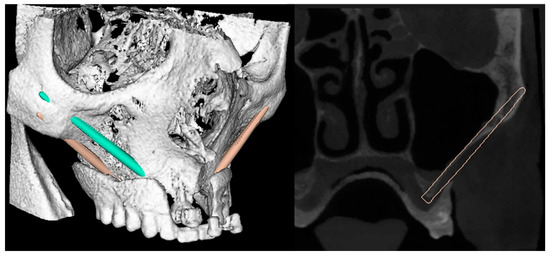

2. Case Report

- Step 2. Software planning of the implant position.